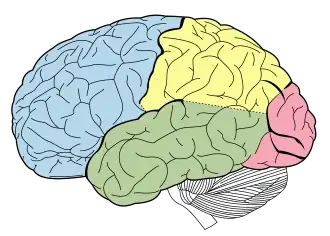

Cognitive neuropsychology is a branch of cognitive psychology that aims to understand how the structure and function of the brain relates to specific psychological processes. Cognitive psychology is the science that looks at how mental processes are responsible for the cognitive abilities to store and produce new memories, produce language, recognize people and objects, as well as our ability to reason and problem solve. Cognitive neuropsychology places a particular emphasis on studying the cognitive effects of brain injury or neurological illness with a view to inferring models of normal cognitive functioning. Evidence is based on case studies of individual brain damaged patients who show deficits in brain areas and from patients who exhibit double dissociations. Double dissociations involve two patients and two tasks. One patient is impaired at one task but normal on the other, while the other patient is normal on the first task and impaired on the other. For example, patient A would be poor at reading printed words while still being normal at understanding spoken words, while the patient B would be normal at understanding written words and be poor at understanding spoken words. Scientists can interpret this information to explain how there is a single cognitive module for word comprehension. From studies like these, researchers infer that different areas of the brain are highly specialised. Cognitive neuropsychology can be distinguished from cognitive neuroscience, which is also interested in brain-damaged patients, but is particularly focused on uncovering the neural mechanisms underlying cognitive processes.[1]